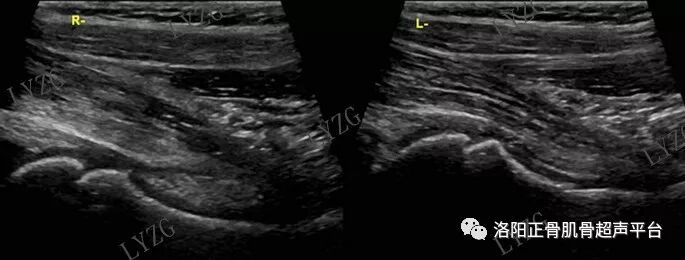

双侧对比,右髋关节前隐窝内未见大于2mm积液,左髋关节前隐窝内积液并可见丝带状滑膜增生

左髋关节前隐窝内及股骨头前方关节腔内均可见积液并可见少量团块状滑膜增生